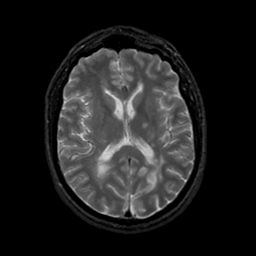

MR Study #22, December 1, 1991 -- Slice #28

[Home][Help][Clinical][Tour 1][Tour 2] Slice 28